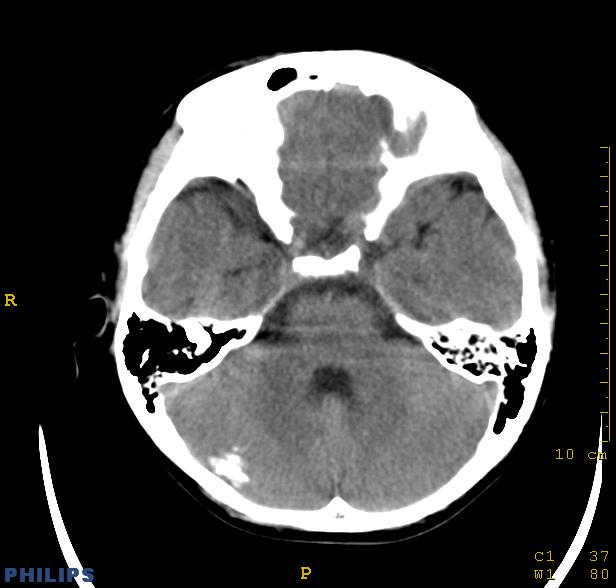

标题: PED0043:头颅平扫 男12岁.典型结节性硬化 [打印本页]

标题: PED0043:头颅平扫 男12岁.典型结节性硬化

典型结节性硬化

[病因病理]

结节硬化是常染色体显性遗传缺陷或基因突变引起的疾病,脑部病理可见神经胶质增生性硬化结节,位于大脑皮质、基底核及侧脑室壁的室管膜下。结节质地较硬,多有钙化。室管膜下结节可演变为巨细胞星形细胞瘤,亦可发生皮质错构瘤,常合并有其他器官畸形和肿瘤。

[影像学表现]

1.ct表现:

①室管膜下有多发性小结节状钙化影,也可为单发、不强化;小结节亦可未钙化;突入脑室可以强化;但有钙化者居多,颅内异常钙化高达90%。一般出生后2年即呈典型钙化。

②10%-15%的病例可能恶变为室管膜下巨细胞星形细胞瘤或其他胶质瘤。前者常位于室间孔附近,生长缓慢,增强扫描可产生异常强化。

③可见白质区脱髓鞘的低密度区。

④可伴脑灰质异位。

⑤脑室扩大系阻塞性脑积水或脑发育不良所致。